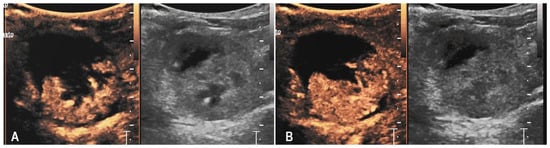

3.3. Case 3